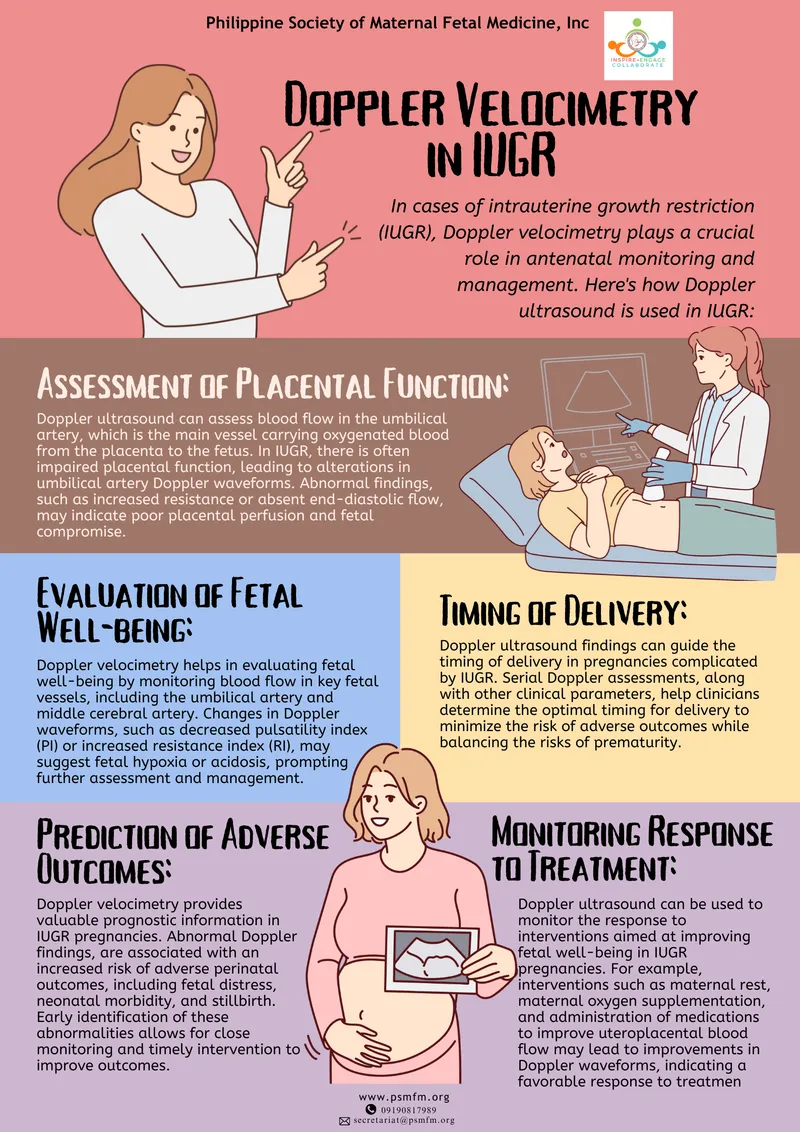

- Intrauterine Growth Restriction (IUGR)/SGA: Estimated Fetal Weight (EFW) < 10th percentile.

- Monitor: Serial USG, Doppler (Umbilical Artery - UA, Middle Cerebral Artery - MCA).

- Delivery: Timed by Doppler severity (e.g., UA absent/reversed end-diastolic flow).